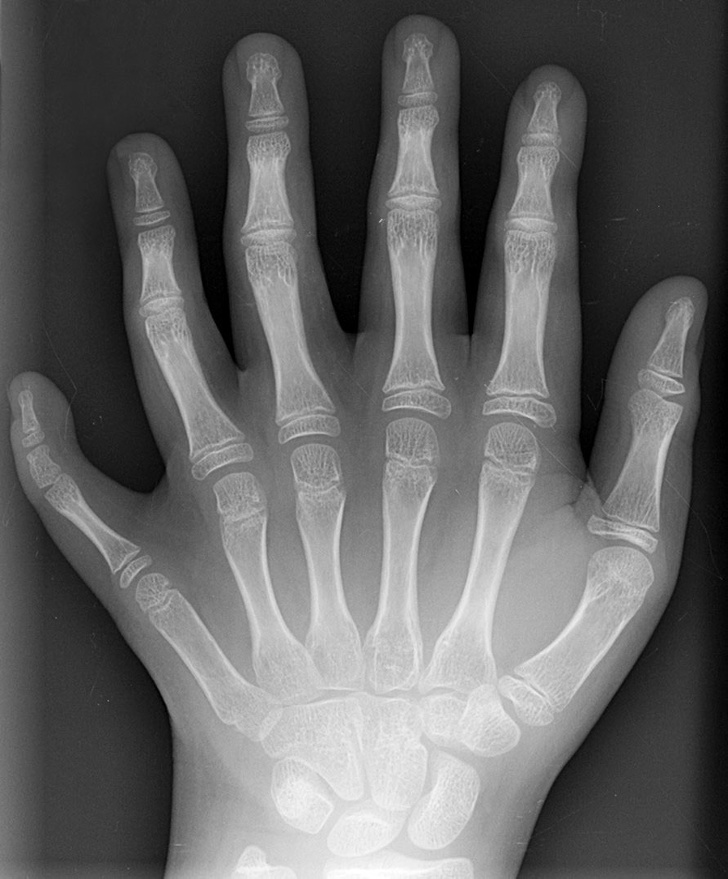

9. Рентгенівський знімок руки дорослої людини і дитини